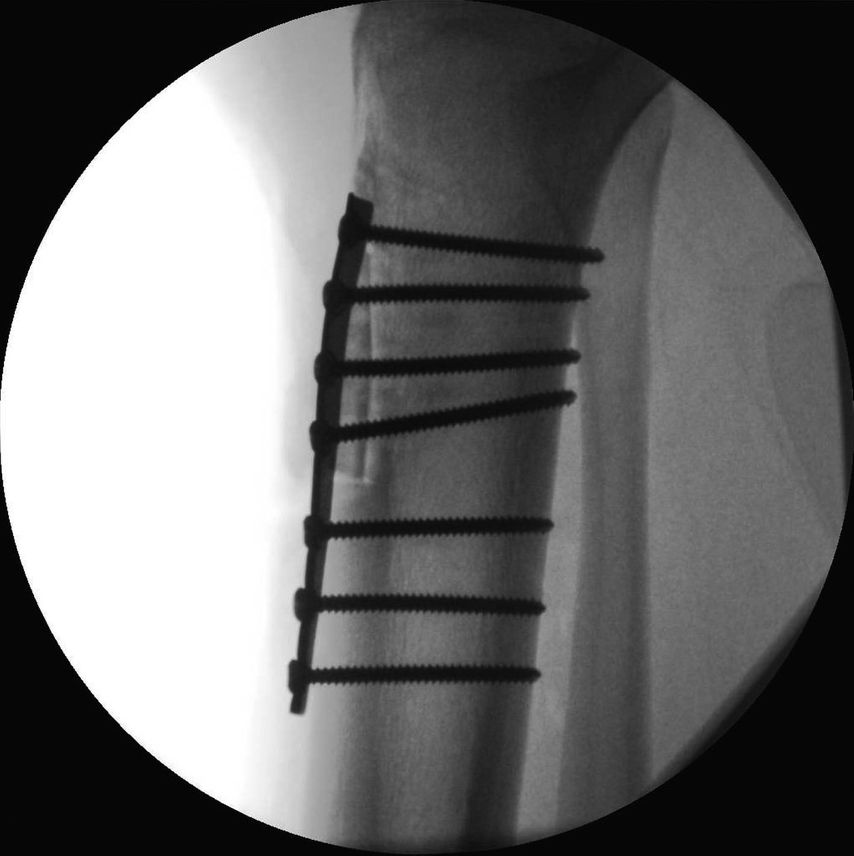

17-jähriger Patient mit wiederkehrenden Patellaluxationen

Aufgrund eines erhöhten Caton-Deschamps-Index von >1,2 erfolgten die Tuberositasdistalisierung und die MPFL-Plastik mit der Gracillissehne (Abb. 2 und 3). Ca. 4 Wochen nach dem operativen Eingriff stürzte der Patient auf das rechte Kniegelenk mit Mehrfragmentbruch des Tuberositasfragments (Abb. 4). Die neuerliche Fixierung erfolgte mittels 3,5mm-Drittelrohrverplattung sowie, wegen des Mehrfragmentbruches im proximalen Bereich, mittels Durchflechtungsnaht und Knochenankern (Abb. 5).

Abb. 5: Intraoperatives Bild nach Verplattung und Zügelung mittels Durchflechtungsnaht und Knochenankern